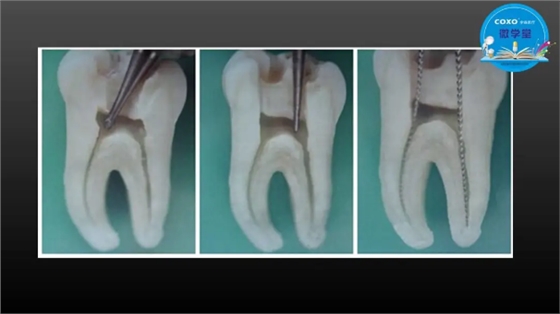

主任医师,牙体牙髓副主任, 广东省口腔医院牙体牙髓科 主任医师。2003年硕士研究生毕业,研究方向为牙体牙髓病学,擅长于牙体牙髓病的诊断、龋齿、牙髓炎、根尖周病的治疗以及前牙美容修复。